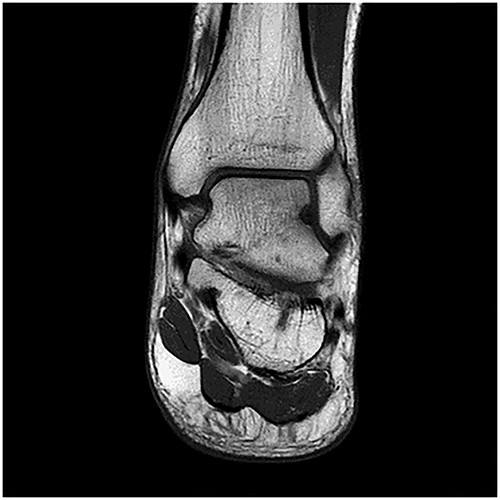

A 28-year-old male patient presented with a history of ankle pain and difficulty with weight-bearing activities on the right side. Radiographic evaluation revealed a large osteochondral defect in the talus. (Figs 1–3).